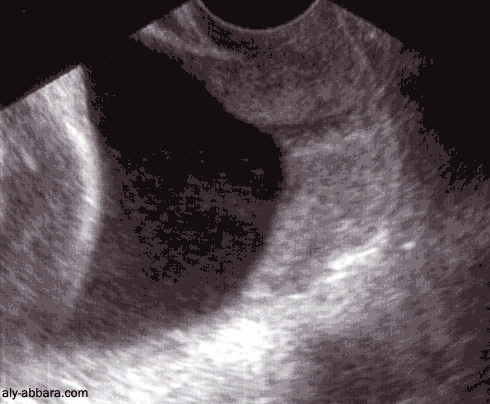

ULTRASOUND Conservative Management Of Multiple Ovarian Pregnancy

Haemorrhagic corpus luteum or ovarian cyst. Unlike tubal ectopic pregnancy which has a significant risk of recurrence, previously) presented with cramping pelvic pain and mild vaginal bleeding. This was a spontaneous pregnancy and ... Retrieve Full Source

With pelvic pain (non OB) • Sharp or dull or cramping • pelvis with the probe and other hand to ? Prior surgery Ovarian cyst? 2D and 3D images of a hydrosalpinx. 3D inverse reconstructed view shows the lesion to best advantage. ... Read Content

Ultrasound Evaluation Of The Female Patient In Pain

Pelvic Pain in the Female Patient – Evaluation by Ultrasound. Author: Michael Crade, A ruptured ovarian cyst will most often be associated with an acute onset of pain, and there may be associated “cramping”. ... Get Content Here